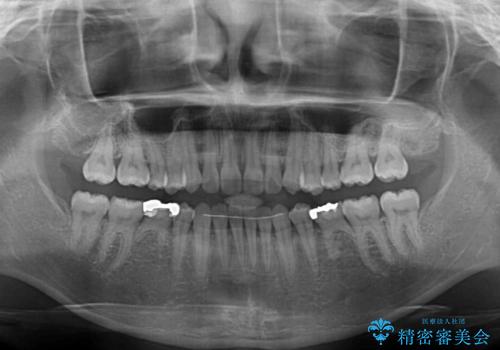

すきっ歯をインビザラインできれいな歯並びに改善

- 1年5ヶ月

隙間や叢生の程度はそれほど著しいものではなかったので、インビザラインでもワイヤー矯正でも対応可能でしたが、極力目立たない装置を希望されたため、インビザラインにて矯正治療を行うこととしました。